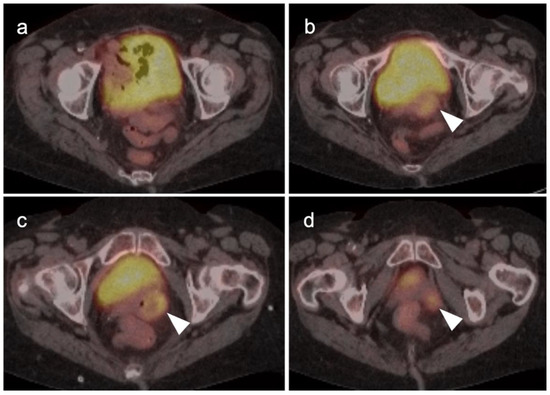

2.6. Vulvar Carcinoma